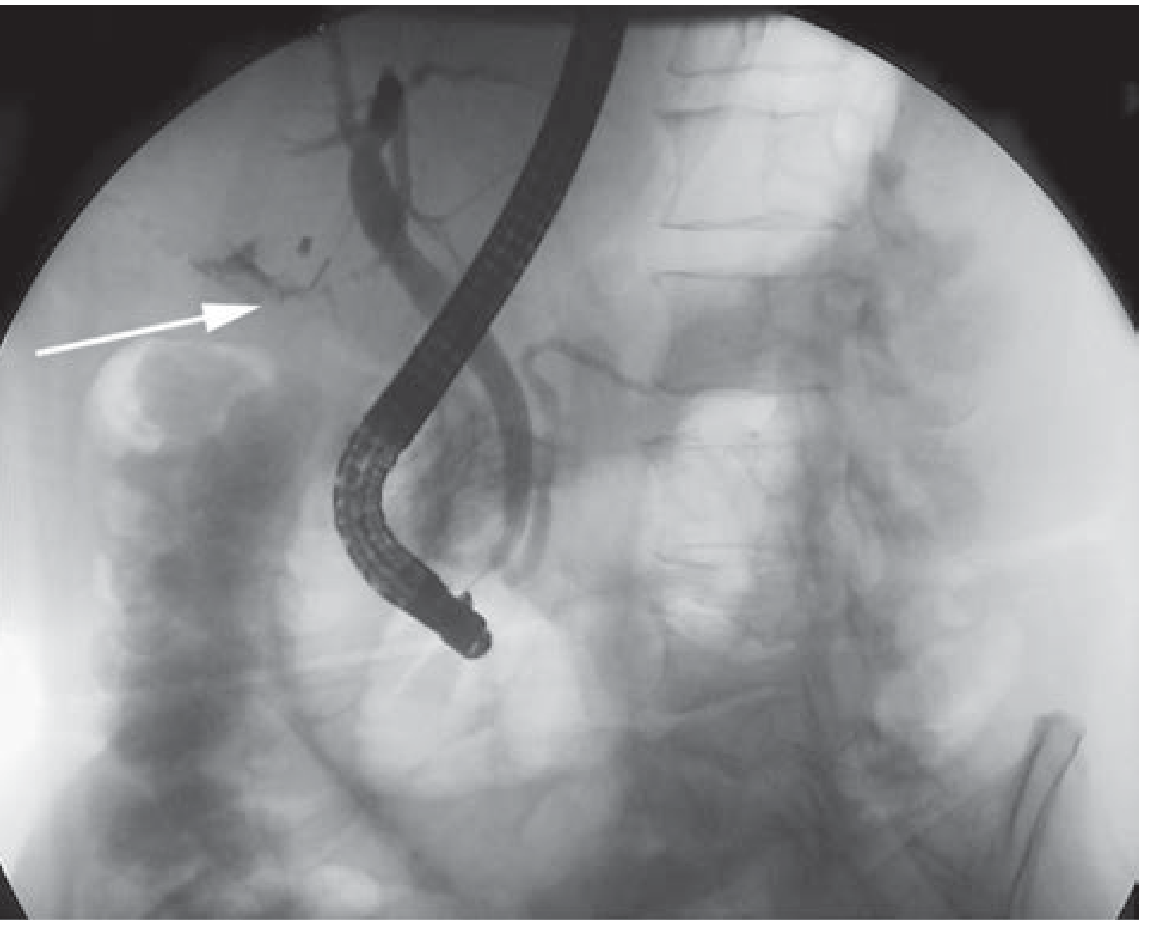

ERCP — Contrast Extravasation from Cystic Duct Stump

(Schwartz's Principles of Surgery, 11e)

ERCP showing contrast extravasation from cystic duct stump (arrow) — note filling of the pancreatic duct

Figure B — Same patient as CT above. ERCP demonstrates contrast extravasation from the cystic duct stump (white arrow). ERCP with sphincterotomy ± stenting is the primary treatment for high-output leaks.